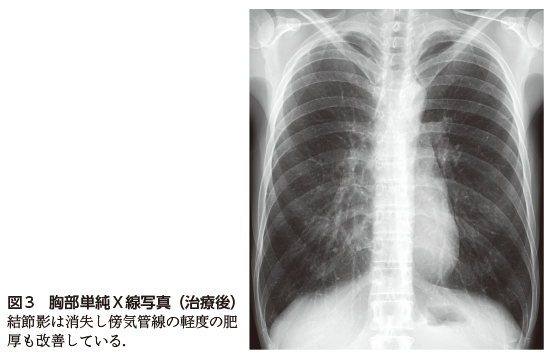

胸部の異常陰影

90D37 | 胸部エックス線 国試 | M3E Medical,60歳代女性。胸部異常陰影:Cadetto.jp,解答・解説】胸部異常陰影にて紹介受診した40 歳代女性|実践!画像診断Q&A|羊土社:レジデントノート - 羊土社,レッスン12◇異常陰影を指摘せよ(難易度 中)(2ページ目):日経メディカル,胸部レントゲンにおける縦隔の陰影について - Genspark